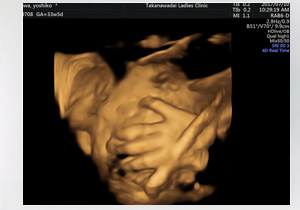

3d 4dエコー 高輪台レディースクリニック 港区の産科 婦人科 女医

3d 4dエコー 高輪台レディースクリニック 港区の産科 婦人科 女医

3d 4dエコー 高輪台レディースクリニック 港区の産科 婦人科 女医

3d 4dエコー 高輪台レディースクリニック 港区の産科 婦人科 女医

3d 4dエコー 高輪台レディースクリニック 港区の産科 婦人科 女医